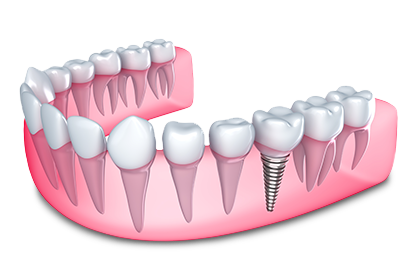

L’implant dentaire, quant à lui, est une procédure qui consiste à remplacer une dent manquante par une dent artificielle. Cette procédure se fait en plusieurs étapes. Après avoir l’empreinte nécessaire à la confection de la couronne (la dent artificielle), il faudra d’abord insérer une tige en titane dans l’espace vacant. Graduellement, la tige adhérera à l’os de la mâchoire de façon permanente. Une fois que la tige sera soudée, on procèdera à l’installation du pivot et de la couronne.

La couronne aura toute l’apparence et la dureté d’une véritable dent et restera définitivement en place. Il faudra prendre soin de cette dent tout comme du reste de vos dents d’ailleurs. Un brossage quotidien et une utilisation régulière de la soie dentaire seront donc de mise.

L’implant a plusieurs avantages. Il permet d’éviter la perte osseuse et le recul des gencives qui survient généralement avec la perte des dents. De plus, il laisse les dents adjacentes entièrement intactes (contrairement au pont conventionnel, qui nécessite leur taillage).